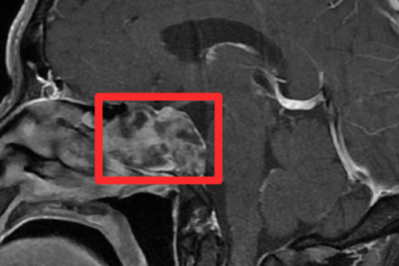

鼻内镜「精准拆弹」,中大医院专家微创切除颅底脊索瘤